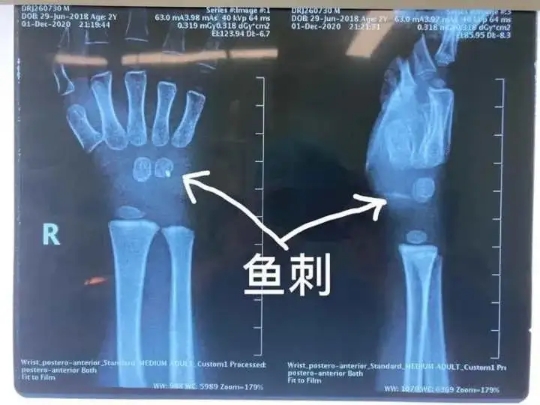

近日,杭州市兒童醫(yī)院骨科還接診了一名被魚刺扎傷手腕的小患者

原來,調(diào)皮的元元(化名)在家拿著魚玩耍,結(jié)果不小心忽然摔倒,魚刺深深地扎進(jìn)了他的手腕。

醫(yī)生拍片檢查后發(fā)現(xiàn),魚刺已經(jīng)深及元元的手腕內(nèi)部約一厘米左右的位置。雖然體表傷口細(xì)小,但是內(nèi)部傷口附近神經(jīng)、血管交織錯(cuò)雜,如不及時(shí)取出魚刺,會嚴(yán)重影響孩子的手腕功能。

手術(shù)室里,骨科醫(yī)生小心翼翼地取出魚刺后,再次探查周圍神經(jīng)、血管、肌腱,確定沒有殘留及其他損傷后,縫合傷口。經(jīng)過兩個(gè)多小時(shí),終于為孩子解決這惱人的“不速之客”。